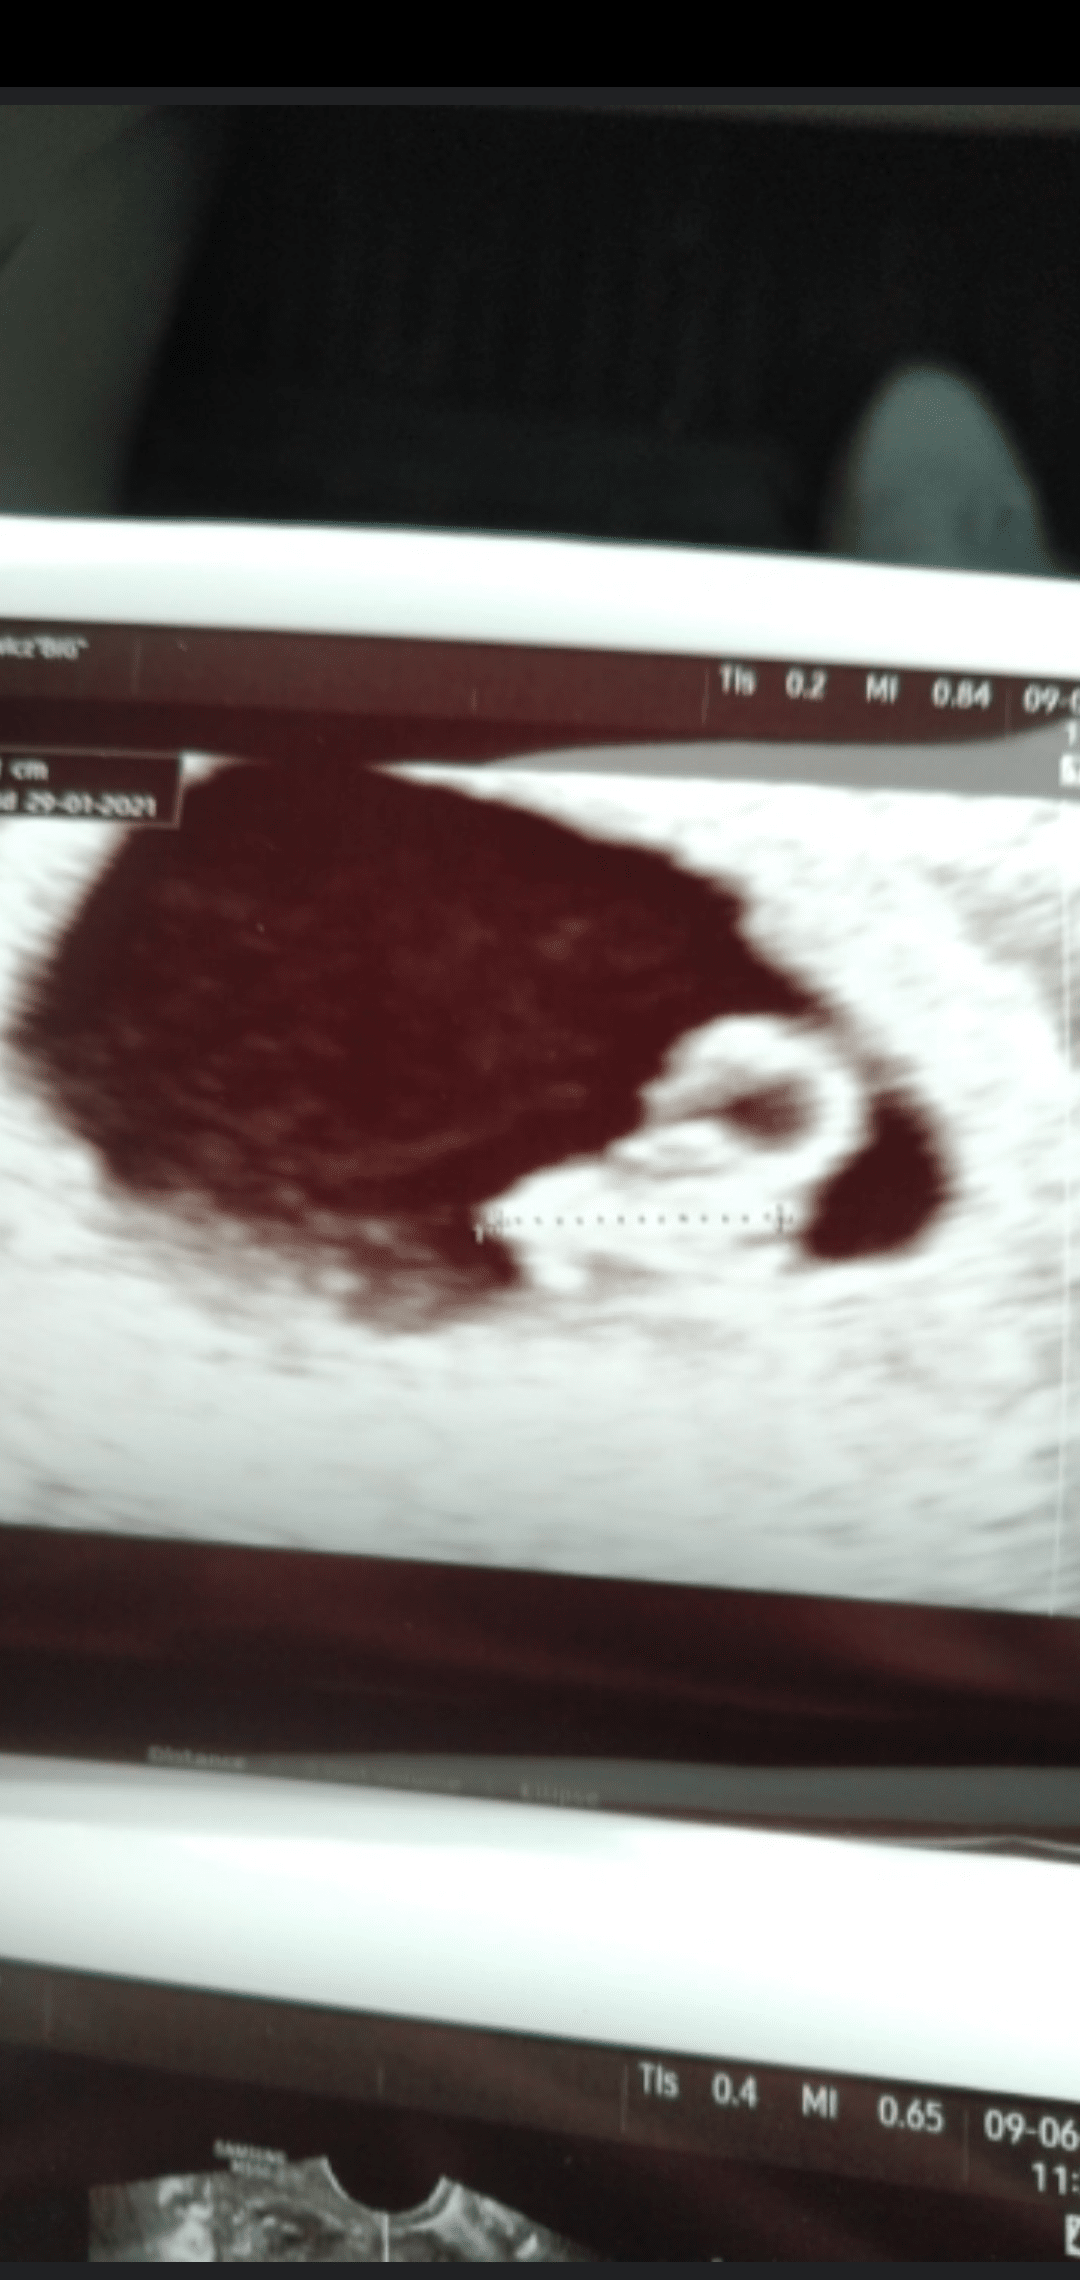

Tak wygląda zarodek , a obok niego, to z pustymi środkiem jest pęcherzyk żółtkowy. Ta kropeczka u ciebie to struktura pęcherzyka.